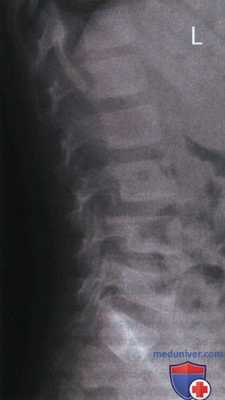

РИСУНОК 1 Рентгенограмма поясничного отдела позвоночника в боковой проекции, демонстрирующая правильное его расположение.

• Визуализируются межпозвонковые отверстия. Остистые отростки видны в профиль

• Корни дуг позвонков, задние края тел позвонков справа и слева накладываются друг на друга (рис. 3)

• Отсутствуют дисторсия тел позвонков (рис. 4 и 5)

• Поясничный отдел позвоночника находится в нейтральном положении между сгибанием и разгибанием

• Экспозиционное поле 20x35 см: позвонок L3 находится в центре экспозиционного поля

• Экспозиционное поле 20x43 см: позвонок L4 и гребень подвздошной кости находятся в центре экспозиционного поля

• Экспозиционное поле 20x35 см: в экспозиционное поле входят 12-й грудной, 1-5 поясничные позвонки и межпозвонковая щель L5-S1

• Экспозиционное поле 20x43 см: в экспозиционное поле входят 11 и 12 грудные, 1-5 поясничные позвонки и крестец

РИСУНОК 2 Правильное положение пациента для рентгенографии поясничного отдела позвоночника в боковой проекции. РИСУНОК 3 Рентгенограмма поясничного отдела позвоночника в боковой проекции. Правая сторона была повернута назад. РИСУНОК 4 Неправильное положение позвоночного столба и рентгеновского стола. РИСУНОК 5 Рентгенограмма поясничного отдела позвоночника в боковой проекции. Позвоночный столб был наклонен к ПИ. РИСУНОК 6 Положение ЦЛ и поясничного отдела позвоночника при сколиозе. РИСУНОК 7 Рентгенограммы поясничного отдела позвоночника в ПЗ и боковой проекциях при сколиозе. ЦЛ был направлен в сторону выпуклой стороны сколиотической дуги. РИСУНОК 8 Правильное положение пациента для рентгенографии поясничного отдела позвоночника в боковой проекции со сгибанием. РИСУНОК 9 Рентгенограмма поясничного отдела позвоночника в боковой проекции со сгибанием. РИСУНОК 10 Правильное положение пациента для рентгенографии поясничного отдела позвоночника в боковой проекции с разгибанием. РИСУНОК 11 Рентгенограмма поясничного отдела позвоночника в боковой проекции с разгибанием. РИСУНОК 12 Правильное положение ЦЛ и продольной оси светового поля. Звездочками отмечены задний край крыла подвздошной кости и передняя верхняя подвздошная ость. РИСУНОК 13 Экранирование гонад при рентгенографии позвоночника, крестца и копчика в боковой проекции. РИСУНОК 14 Правильное экранирование гонад при рентгенографии позвоночника, крестца и копчика в боковой проекции.